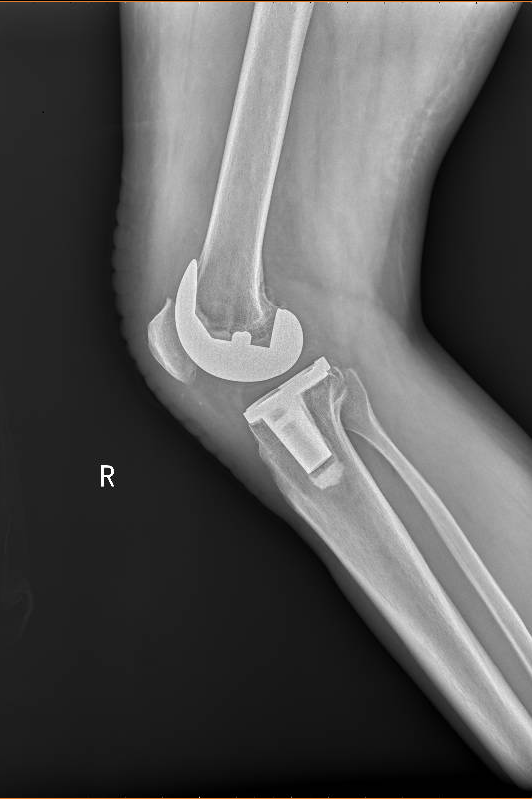

2020年1月初,程珂琳副主任醫師在門診見到了老Tim,看到他一瘸一拐艱難地走進診室,程醫生發現老Tim的病情比想象中還要嚴重。經過認真地詢問病史、查體,結合影像檢查,老Tim被確診為老年性雙膝骨性關節炎,程醫生表示可以通過手術有效緩解疼痛,并且配合術后的康復治療,患者能恢復正常行走。完善了相關檢查以后,1月10日,老Tim住進了關節骨病科,并于次日接受了手術治療。手術由關節骨病科、麻醉科等科室共同完成,程珂琳副主任醫師及其團隊僅用1個小時就成功地為老Tim實施了人工膝關節表面置換術,手術快而精準。

術前

術后